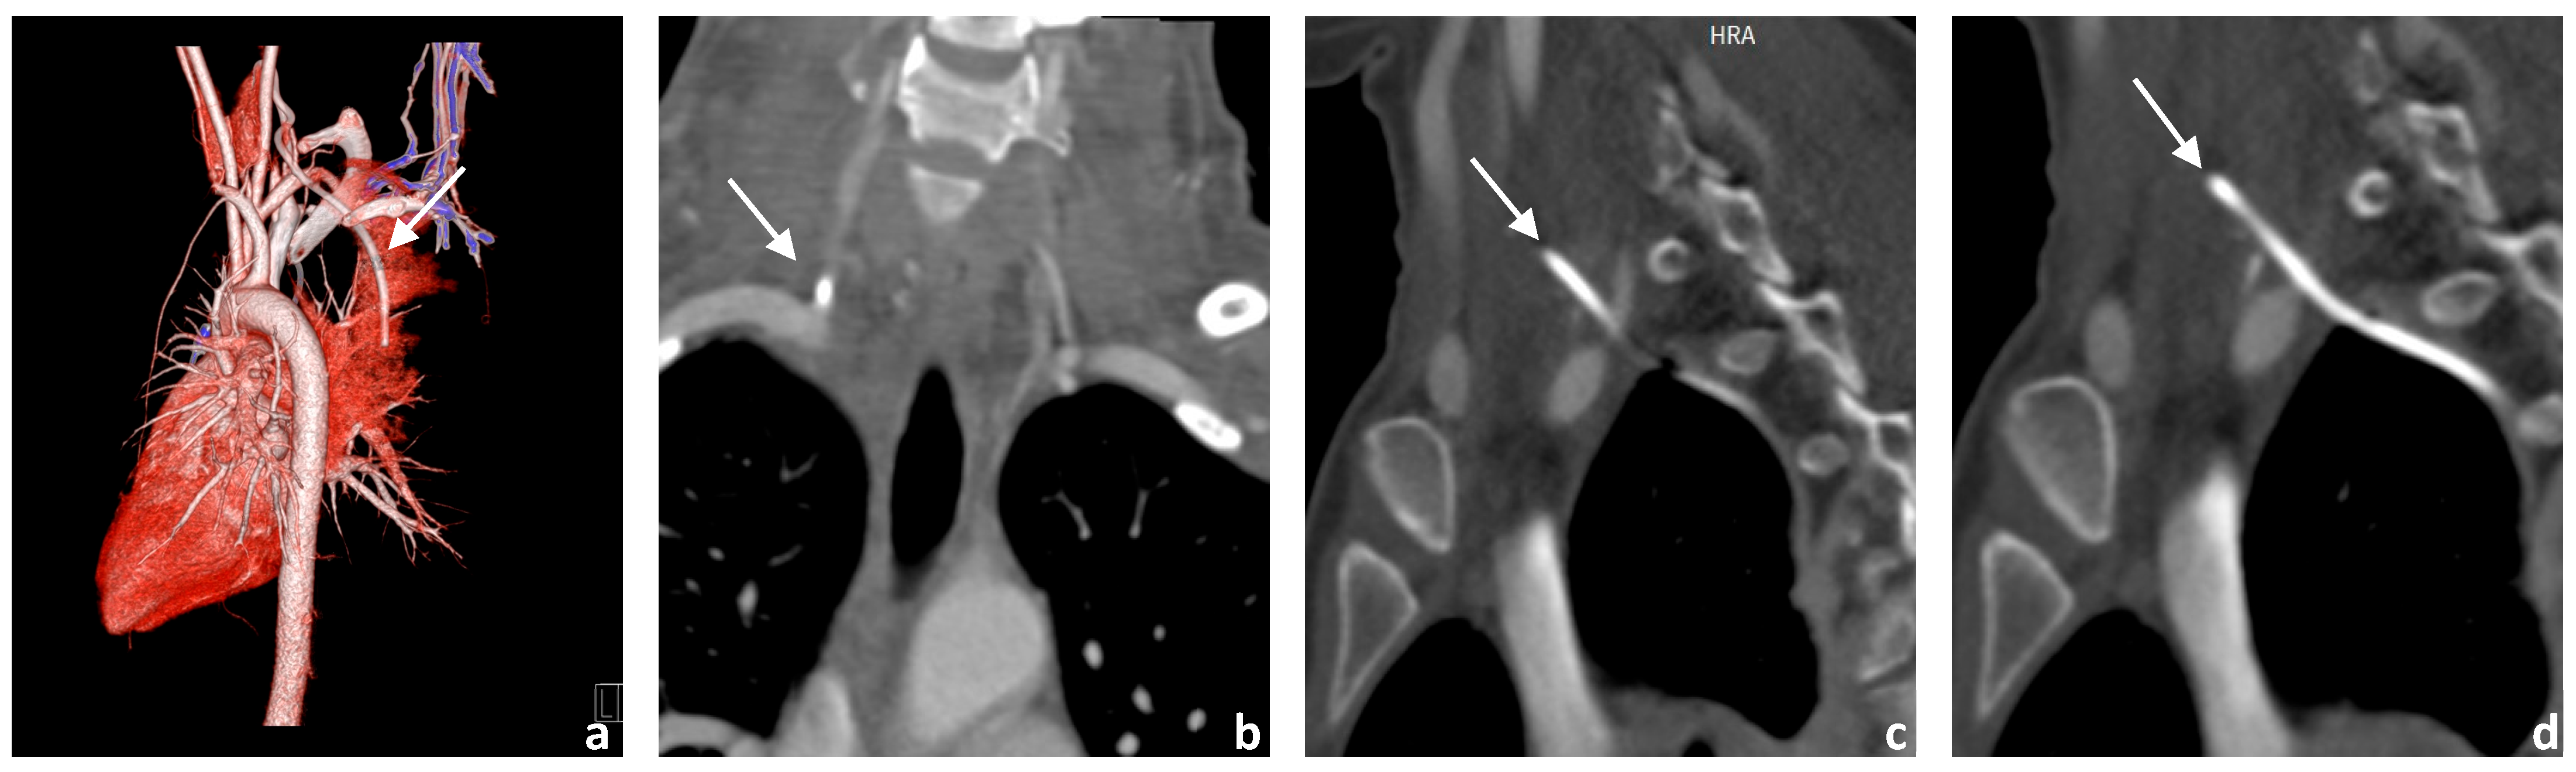

3.1. Image Acquisition

3.2. Neurointerventional Procedure

3.4. Postinterventional Result